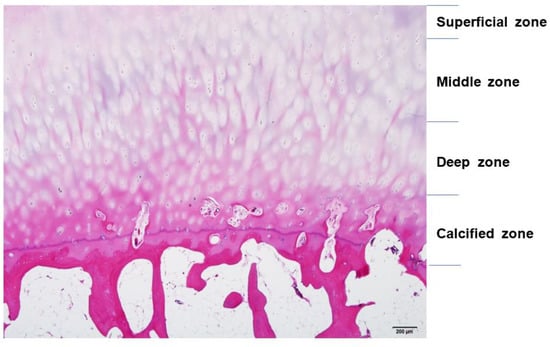

Articular cartilage is a thin, viscoelastic layer of connective tissue 2–3 mm thick [9] (Figure 3). It is of mesodermal origin and is characterized by a cellular component immersed within an extracellular matrix composed of polysaccharides, fibrous protein, and interstitial fluid [10]. The cartilage has no direct supply of blood, nerve signals, or nutrition and relies on diffusion through the surrounding tissues.

Figure 3. The structure of articular cartilage, comprised of four zones: superficial, middle, deep, and calcified. Among zones, there are differences in collagen fibers, arrangement of chondrocytes, and distribution of proteoglycans and glycosaminoglycans (GAGs). Hematoxylin and eosin staining. Scale bar, 200 μm.